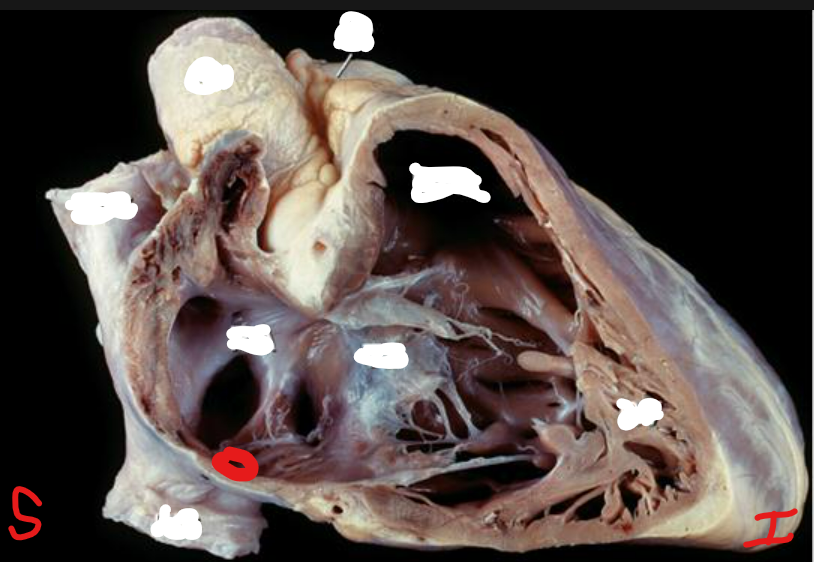

Q

Name this structure. What is the term for the structure it is on?

A

Fossa Ovalis

Interatrial Septum

Name this structure and give the names of all the chambers of the heart that contain it.

Papillary Muscle

Right and Left Ventricles